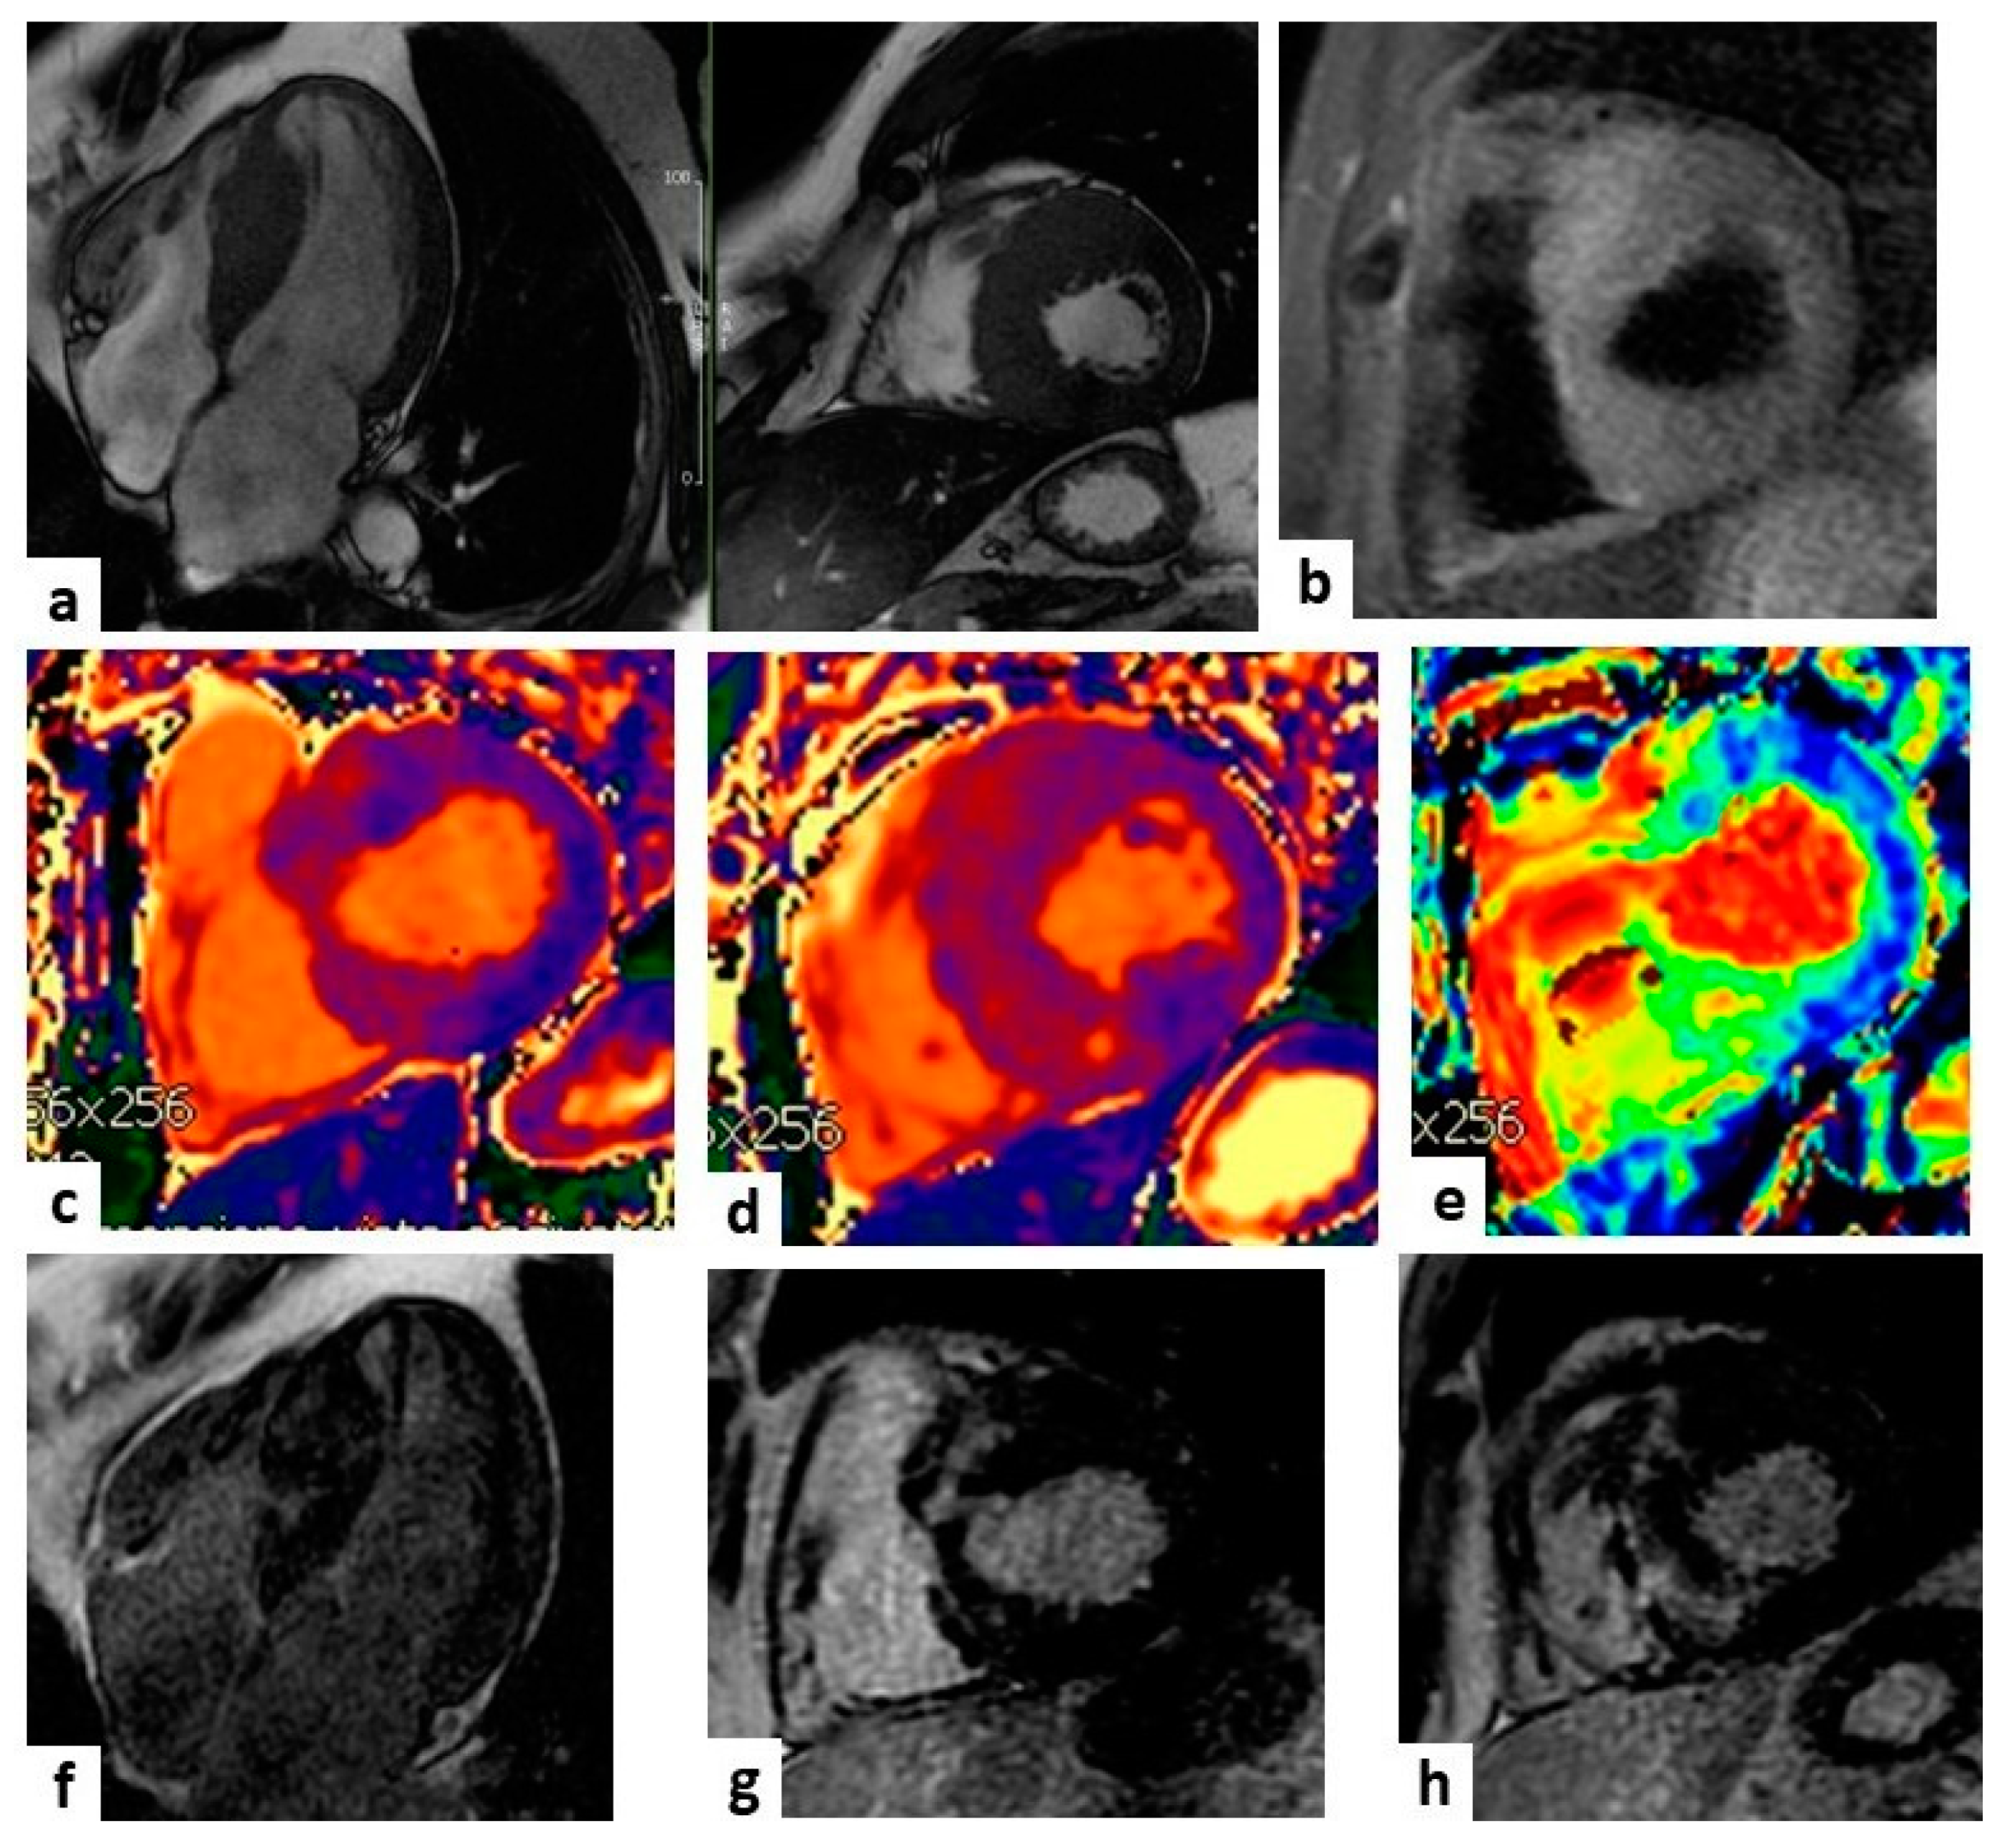

2.1. Morphology and Function

2.2. Tissue Characterization